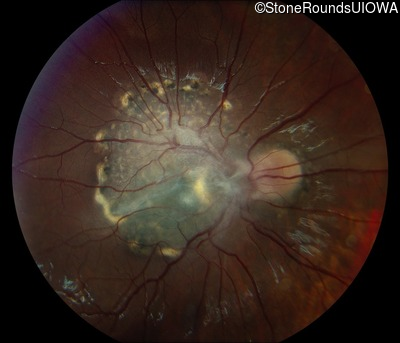

This 9 year old male was noted to have some crossing of his eyes at 2 months of age and the eye exam which followed identified a retinal lesion in the right eye. When he was six years old an epiretinal membrane was noted in his left eye. Two years later it was decided that it was a thin hamartoma in that eye as well. He underwent neuroimaging at age 7 which identified bilateral acoustic neuromas.

| Age at visit: 10 years |

| Age at visit: 11 years |

| Age at visit: 14 years |